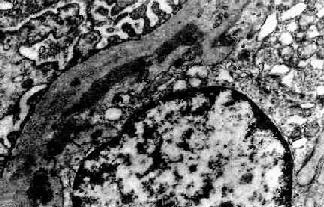

图12-15 膜性增生性肾小球肾炎 Ⅰ型

肾小球毛细血管基底膜内侧,内皮细胞下电子致密沉积物,部分上皮细胞足突消失

Ⅰ型电子致密物沉积在肾小球基底膜内侧,内皮细胞下,大小不等,常聚积成大团块状(图12-14,图12-15)。系膜内和上皮细胞下偶然也可见有少量小而不规则的沉积物。